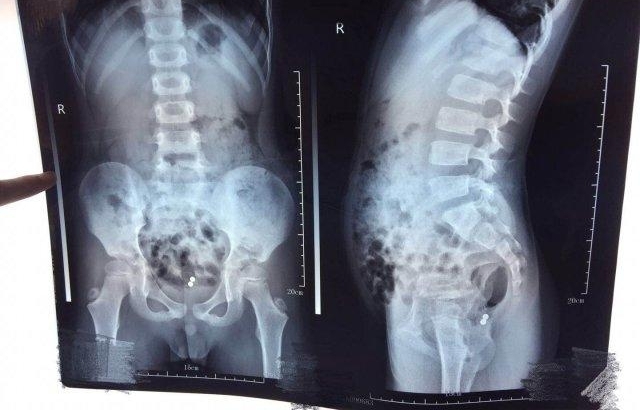

家长带着小林来到大连市中心医院就诊,经检查,腹部放射线检查提示磁力珠相聚较远,暂无吸附导致肠穿孔可能,予以通便药物口服,促其排出,然而并未达到目的。再次就诊是 3 天后,拍片提示两枚磁力珠已经吸附在一起,在直肠壶腹部,医生建议尽快取出。然而由于孩子不配合,并且家长仍认为可能自行排出,结果又等待了 2 天的时间。

症状就在此后发生了,16 日,小林已经出现肛门不适感,于是赶紧又来医院就诊。再次拍片,医生们发现,磁力球的位置几乎没有改变。" 这必须得手术了 " 肛肠外科主任郭旭刚表示。于是家长同意手术后,医生们进行了急诊手术探查。手术时,医生们发现磁力球已经导致直肠穿孔,一枚位于肠内,1 枚位于肠外。于是便进行了取磁力珠后的直肠缝合修补。" 那两枚磁力珠的磁力非常大,要用很大的力气才能够将其分开 " 郭旭刚介绍。手术成功后,又经抗感染、换药等对症治疗后,小林已经于近日顺利出院了。